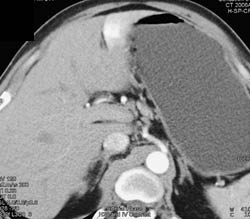

Cholangiocarcinoma With Dilated Ducts